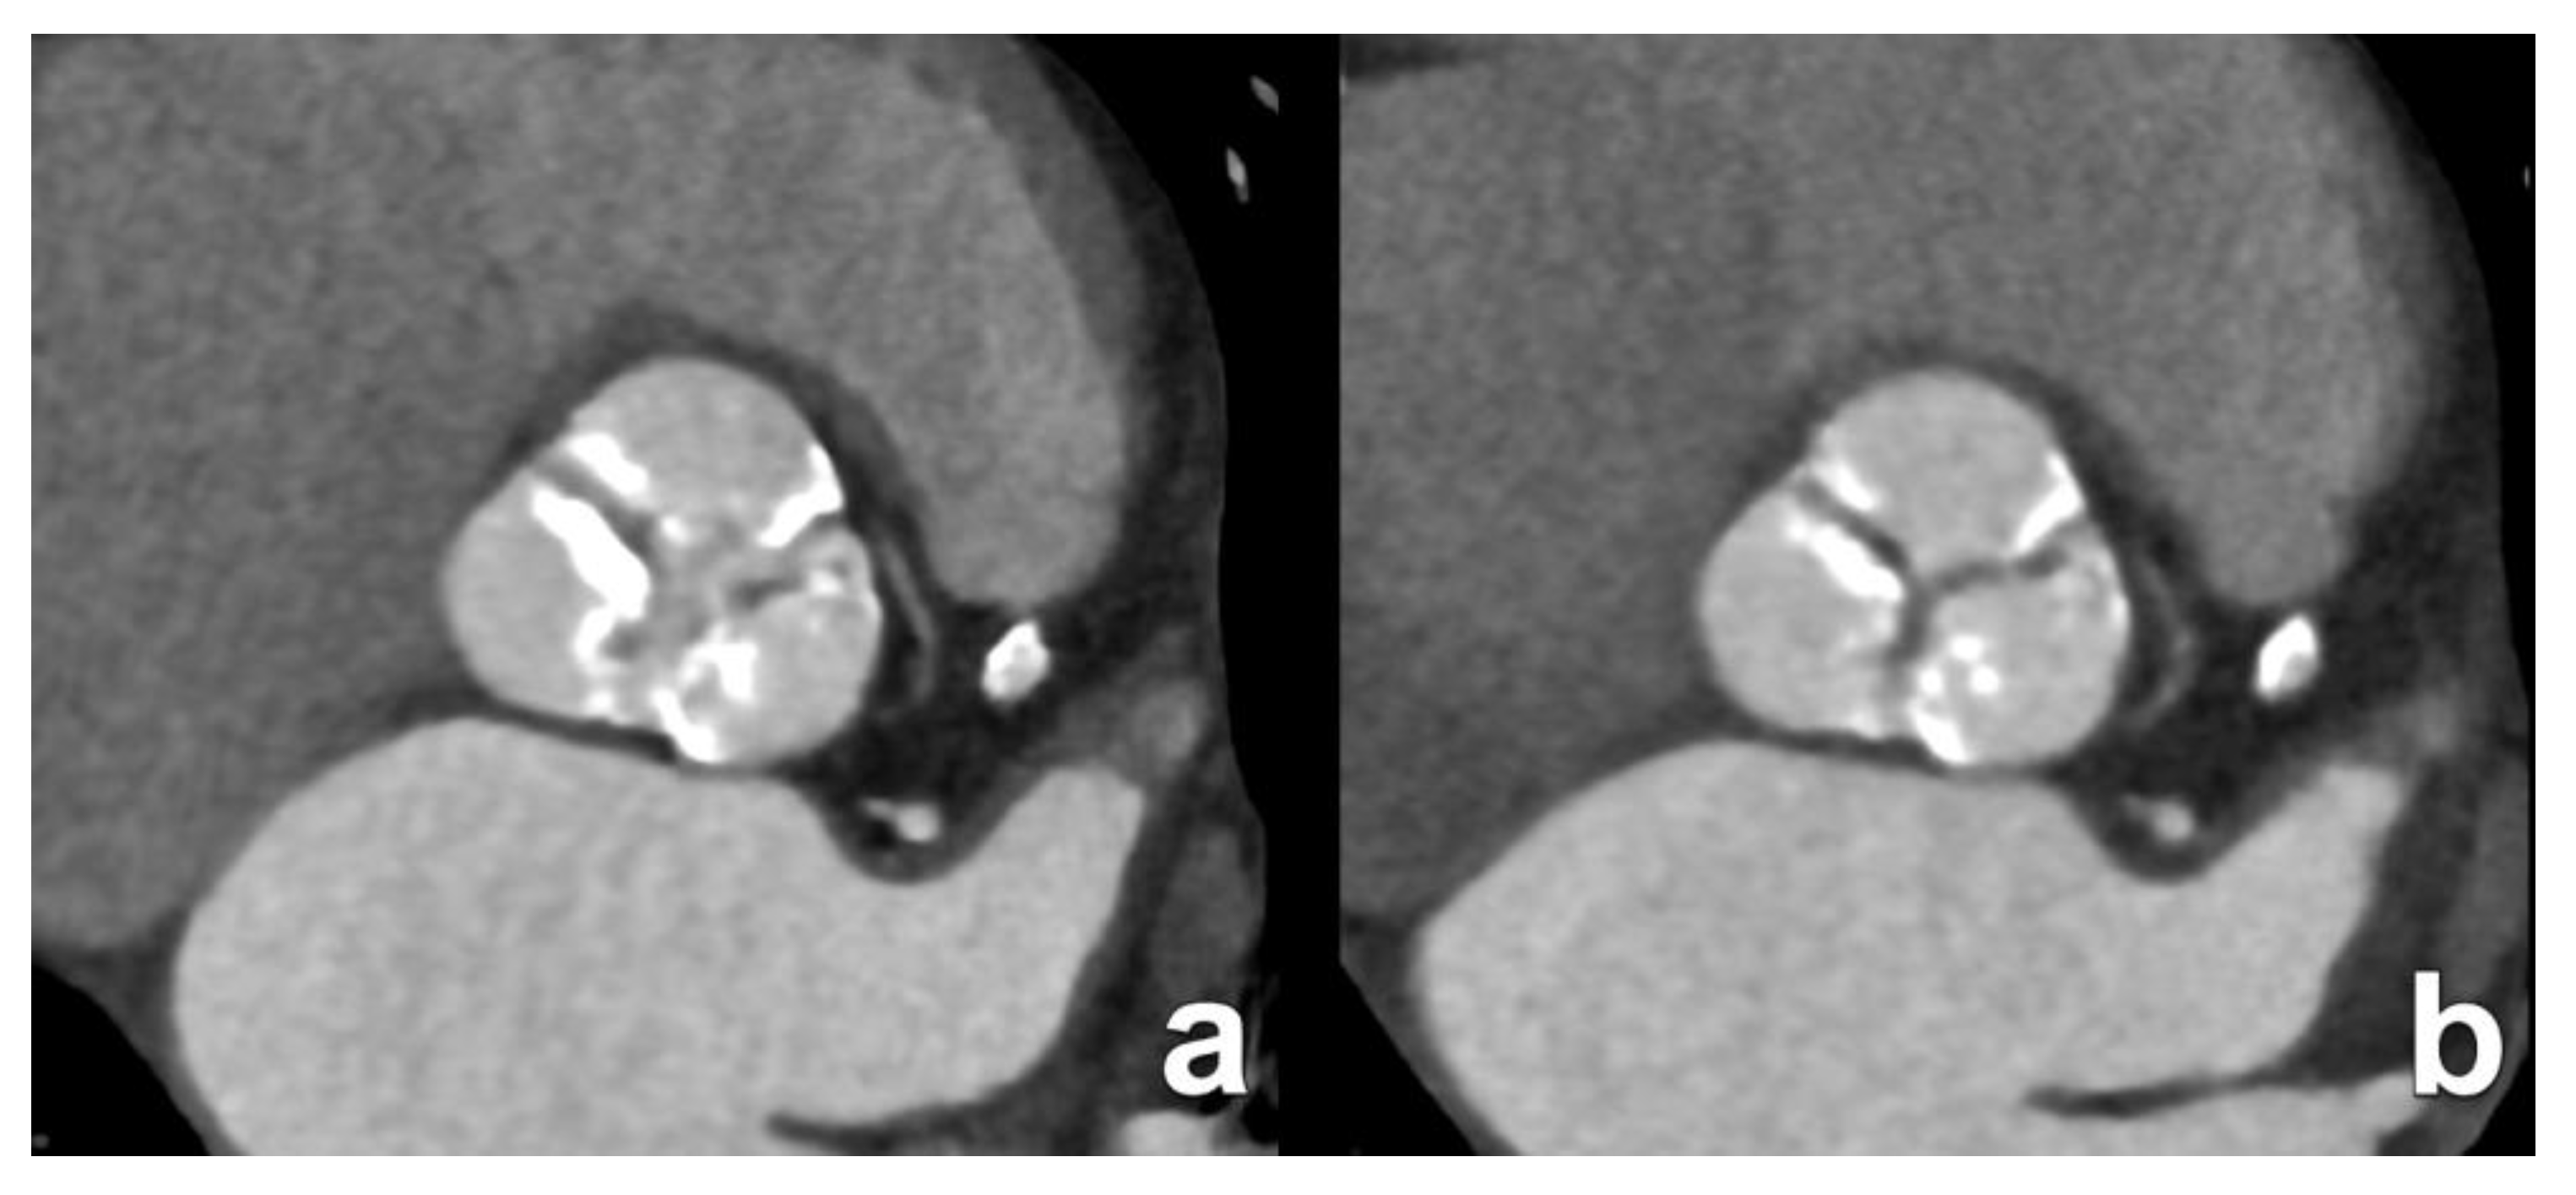

3. Transcatheter Aortic Valve Replacement